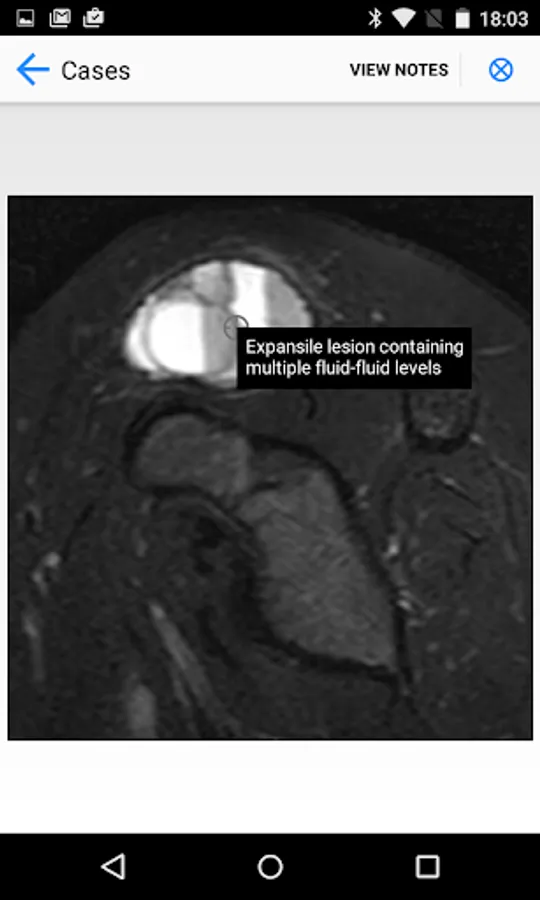

BoSTT brings the user a real experience of frequent and rare, typical and more unusual cases of bone and soft tissue tumours. Each case has a clinical history, high resolution radiology and pathology images, diagnosis, treatment and learning points.